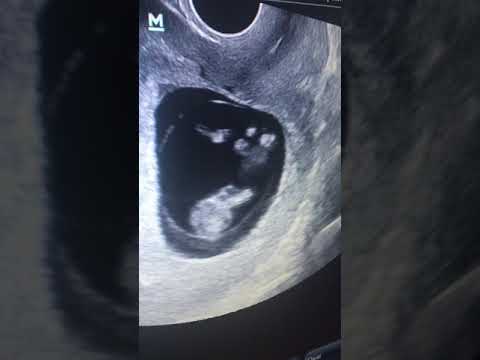

Hellow guys, Welcome to my website, and you are watching Ультразвуковая диагностика органов малого таза обязательна 1 раз в год🫶. and this vIdeo is uploaded by Гинеколог-эндокринолог // врач УЗИ // Дубай at 2023-06-06T20:55:15-07:00. We are pramote this video only for entertainment and educational perpose only. So, I hop you like our website.